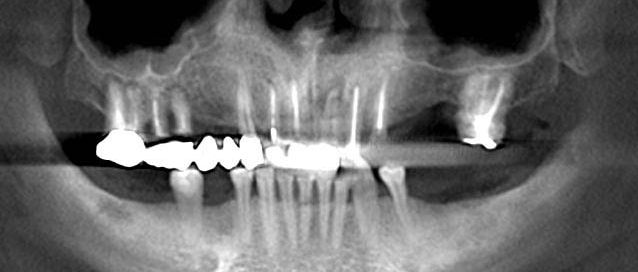

Initial orthopantomography.